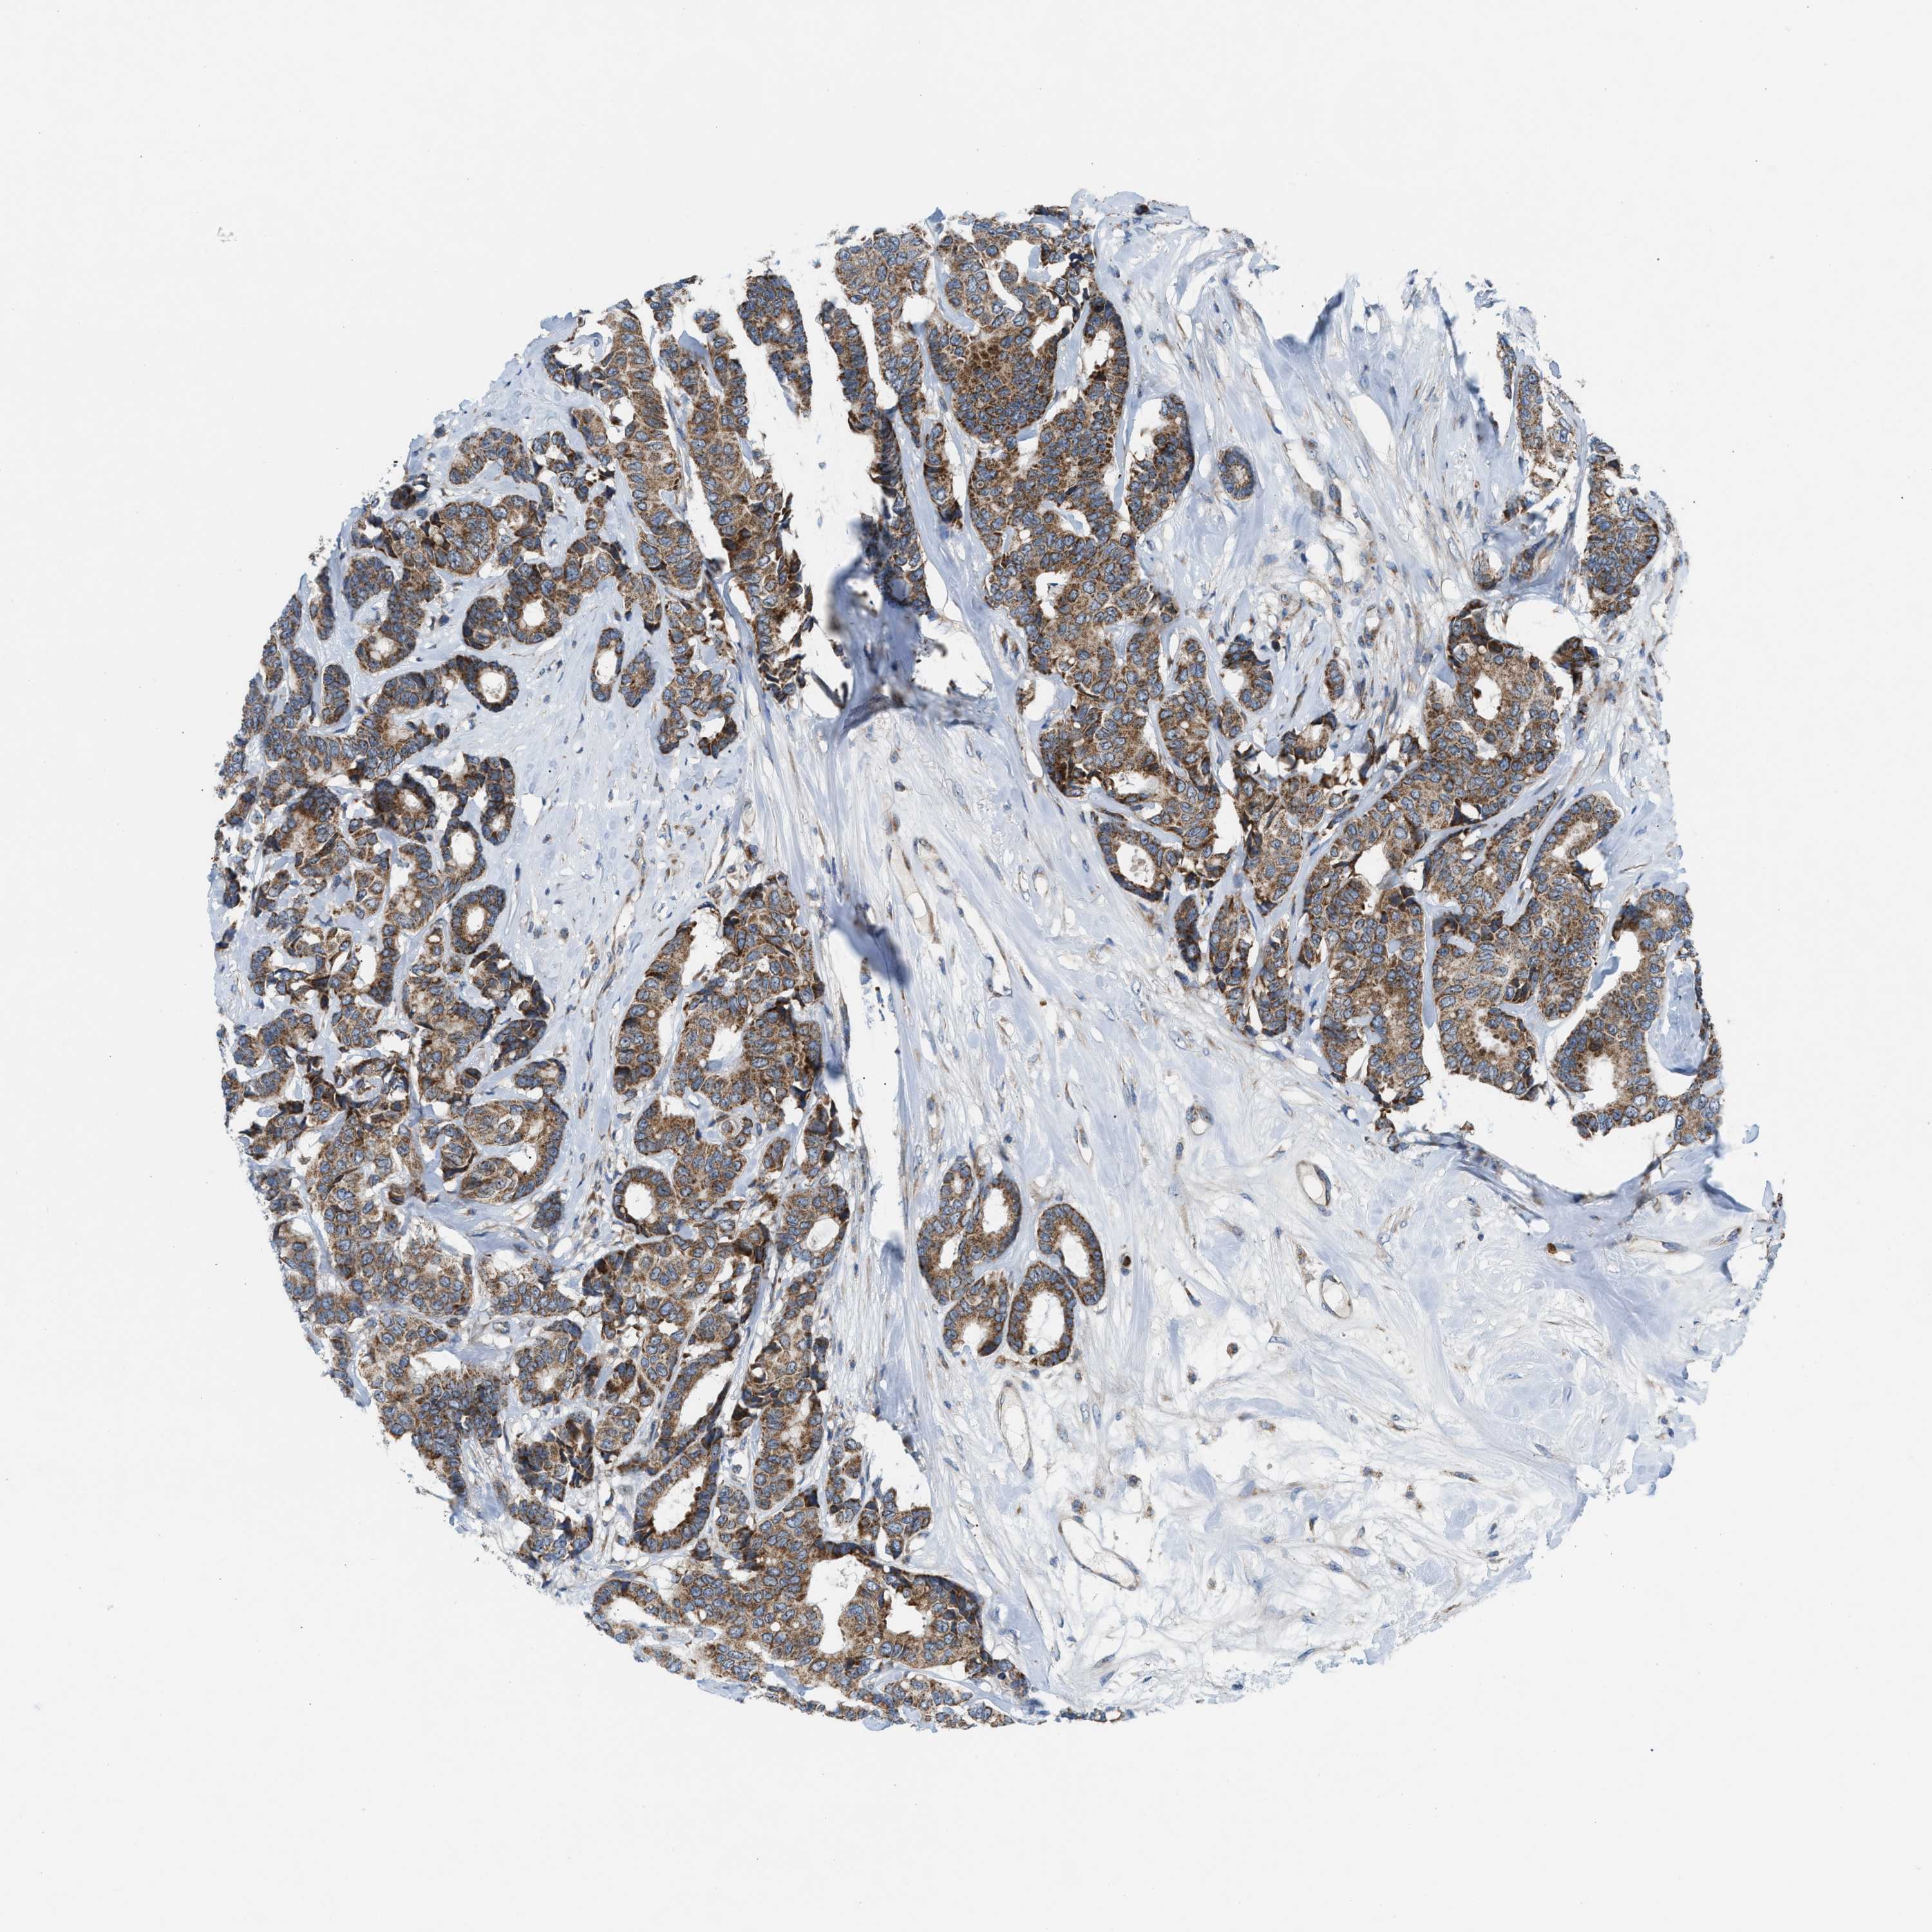

CANCER BREAST CANCER Show tissue menu

BRCA TCGA BRCA VALIDATION PROTEIN EXPRESSION